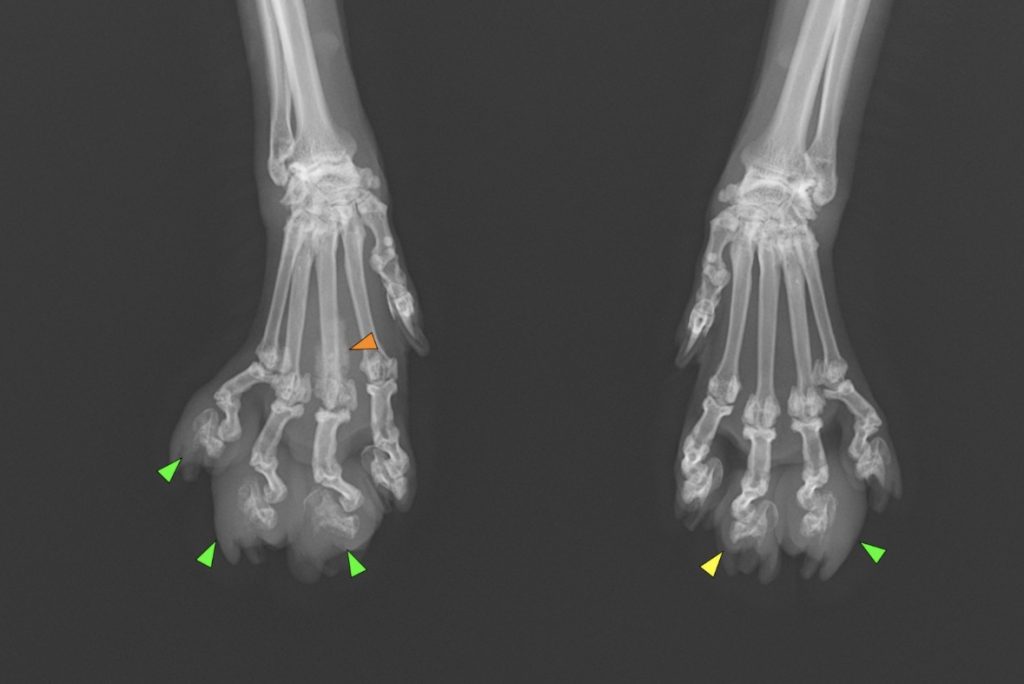

原因を探るために、レントゲンを撮らせていただくことにしました。

腫瘍や炎症の可能性を考えました。特に足や指の腫瘍も考えましたが、左右の前足で同時に症状が出ていることに違和感を感じました。足や指の腫瘍なら、通常は片方の足だけ出ることが多いです。そこで、ある疾患が鑑別疾患に挙がり、肺のレントゲンを撮影しました。

この結果からやはり鑑別疾患に挙げていた肺指(はいゆび)症候群と診断しました。肺指症候群とは、肺癌が四肢の指先に転移する猫ちゃん特有の病態です。

転移なので多発することもあり、足先が腫れ、骨も溶けてくるため、非常に強い痛みを伴います。